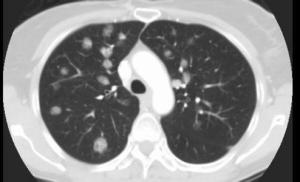

良性淋巴细胞血管炎和肉芽肿病(benign lymphocytic angiitis and granulomatosis,BLAG)于1977年由Saldana等提出,它是一种类似Wegener肉芽肿及淋巴瘤样肉芽肿病的疾病,其病变存在于皮肤及呼吸道,皮肤病变主要表现为慢性反复发作的脂膜炎。根据近20年来的国内外有关文献报告发病率较低,也无明显的地域及季节分布特点,此病属于良性病变,预后良好,经治疗痊愈后的病人长期随诊均无病存活。